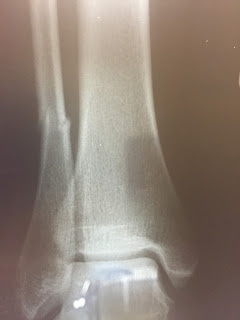

September 2015

I was running at the gym in August and stepped down and my ankle hurt so bad.  I left the gym thinking I had just sprained my ankle.  A few weeks later, it was still hurting so I went to the doctor and it was broken! I spent about a month in a boot.